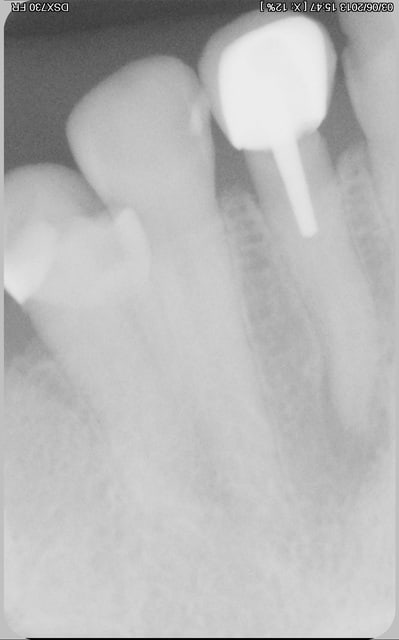

3 MOIS plus tard endo .la pate fuse a l apex et on voit bien qu elle bute sur de l os compact .

7 ablcpx - Eugenol

et meme l os vestibulaire a repoussé donc empreinte pour refaire ccm.

matte la gencive .pas de prov .juste remis son ancienne coiffe bricolée dans les dernier temps .

pas mal non ?

ça tu ne le liras pas dans la bibliotheque rose!